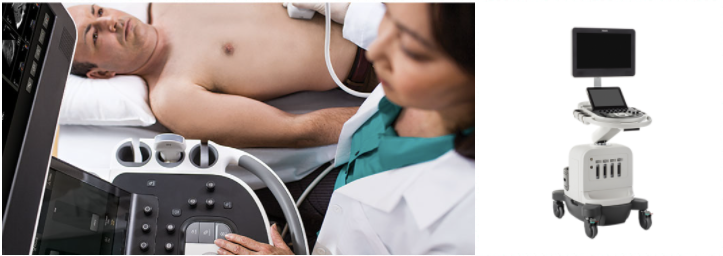

左侧的图片是超声检查的一个例子。医生用手触摸患者的部分是传感器(探针);右侧的图片是飞利浦超声仪器。图片来源飞利浦官方网站。